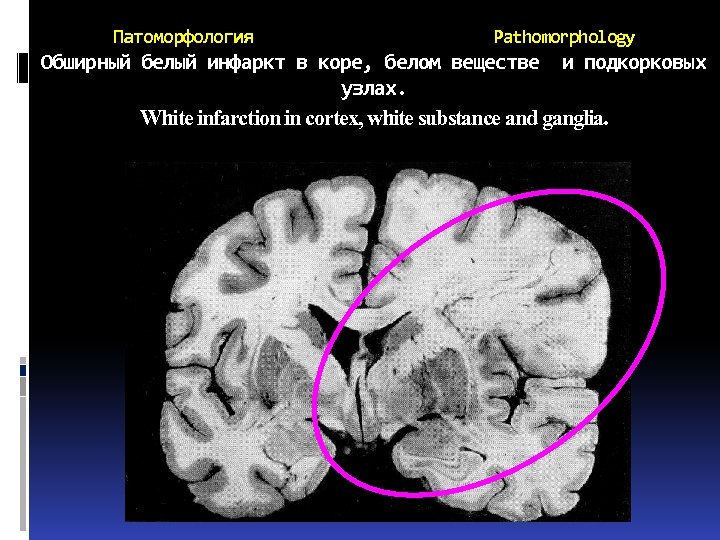

Патоморфология ишемических инсультов Pathomorphology of ischemic s. При ИИ развиваются инфаркты, т. е. очаговые некрозы мозга. Инфаркты могут быть от микроскопических до обширных размеров. Инфаркты мозга бывают: Белыми (серыми) Красными Смешанными Brain infarctions may be White Red Mixed

Патоморфология ишемических инсультов Pathomorphology of ischemic s. При ИИ развиваются инфаркты, т. е. очаговые некрозы мозга. Инфаркты могут быть от микроскопических до обширных размеров. Инфаркты мозга бывают: Белыми (серыми) Красными Смешанными Brain infarctions may be White Red Mixed

Патом огия Белые инфаркты составляют 85 -90%, характеризуются дряблостью, набуханием и побледнением вещества мозга, стушеванностью границ. В дальнейшем происходит ограничение очага, увеличивается дряблость, и вещество мозга в области инфаркта превращается в бесструктурную крошащуюся массу серого цвета.

Патом огия Белые инфаркты составляют 85 -90%, характеризуются дряблостью, набуханием и побледнением вещества мозга, стушеванностью границ. В дальнейшем происходит ограничение очага, увеличивается дряблость, и вещество мозга в области инфаркта превращается в бесструктурную крошащуюся массу серого цвета.

Патоморфология Pathomorphology Обширный белый инфаркт в коре, белом веществе и подкорковых узлах. White infarction in cortex, white substance and ganglia.

Патоморфология Pathomorphology Обширный белый инфаркт в коре, белом веществе и подкорковых узлах. White infarction in cortex, white substance and ganglia.